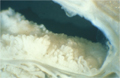

Macroscopic findings (resection specimen, dissecting microscope image):(IPMA: intraductal papillary- mucinous adenoma)Proliferating, papillary lesions are seen within dilated pancreatic ducts (*). Pancreatic duct dilation is typically due to voluminous mucus produced by the tumor.